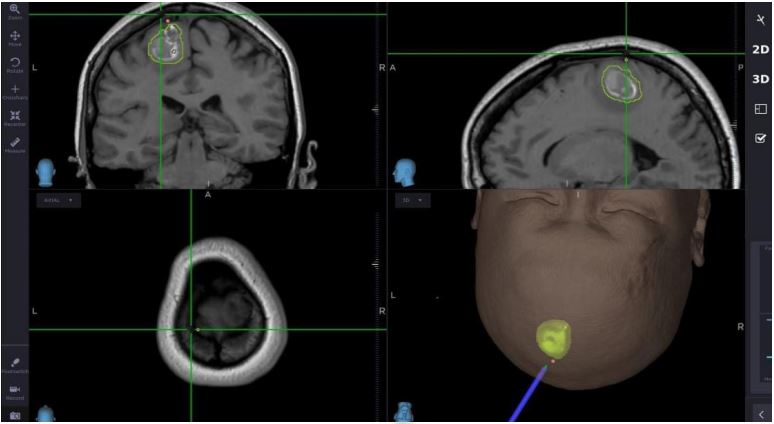

案例(三):血管瘤破裂流血导致肢体无力49岁的女士,接种疫苗后2周感到左腿无力,虽然看了中医和骨科医生,更做了脊柱磁力共振MRI造影, 仍然找不到原因。脑血管外科医生经过临床评估后为她进行了3D三维立体磁力共振脑血管造影,显示其大脑都有先天性动静脉畸形血管瘤并且已经少量出血,瘀血压着她右脑负责控制左腿功能的位置。在3D三维立体电脑导航、运动神经脑皮层反射和连续脑功能监测系统下,神经血管外科医生在显微镜下彻底切除血管瘤和去除瘀血,病人脑部的神经功能得以完好恢复。手术后,病人左腿的力量恢复正常。 | ||

![]() | ||

![]() | ![]() | |

使用运动皮层映射和连续脑功能监测系统进行手术 | ||